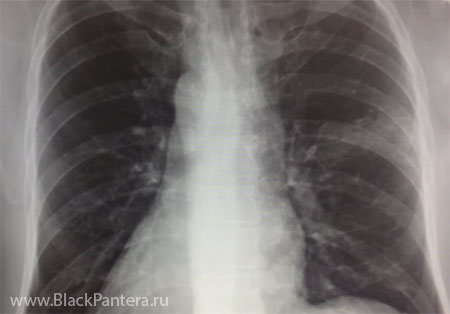

- Даже при легком кашле, ознобе, повышении температуры желательно обратиться за консультацией к врачу. Делать это необходимо потому, что в последнее время участились случаи заболевания пневмонией, которая в первые дни протекает так же, как легкая простуда. Пациенты жалуются на кашель, боли в горле, а буквально через 3-4 дня после начала заболевания резко поднимается температура и развивается обширный воспалительный процесс в легких. Поэтому гораздо безопаснее будет пройти обследование уже при легких симптомах, чтобы обезопасить себя от пневмонии, - сказал доктор Ричард Рассел (г. Лондон, Британия).

Стоит отметить, что самым надежным способом защиты от пневмонии является вакцинация, никаких других методов профилактики заболевания не существует.